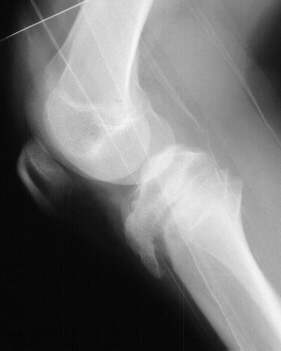

RADIOGRAPHS:

AP and lateral views of the right lower extremity revealed a Salter Harris III proximal tibial fracture with intraarticular extension into the medial and lateral tibial plateaus. The epiphysis was anteriorly displaced on the metaphysis.